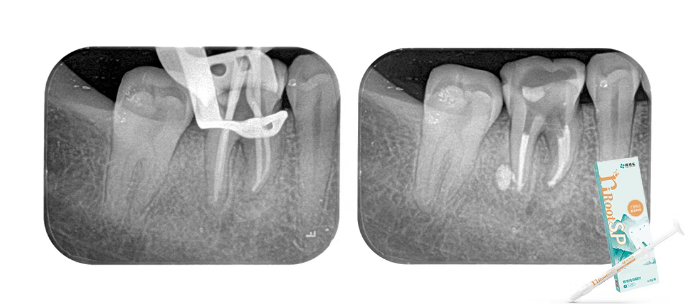

第三次就诊

涡轮机去除封药,3%NaCIO荡洗,蒸馏水置换,试尖,干燥根管,

恩普诺nRootSP单尖法充填,特氟龙+玻璃离子暂封。

2个月复查

治疗后两月完成最终修复,临床检查无症状,行使功能良好;通过根尖片可见根尖低密度暗影有改善,根分叉处及牙周膜增宽影像呈现愈合趋势;

除了糊剂些许溢出外,一切良好,得益于nRootSP良好的性能。